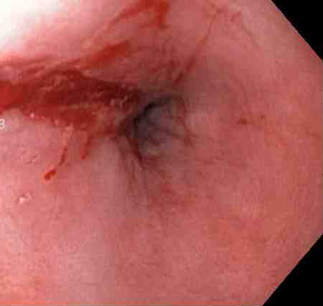

Actively bleeding tear appears as a red longitudinal defect with normal surrounding mucosa

From the collection of Juan Carlos Munoz, MD, University of Florida